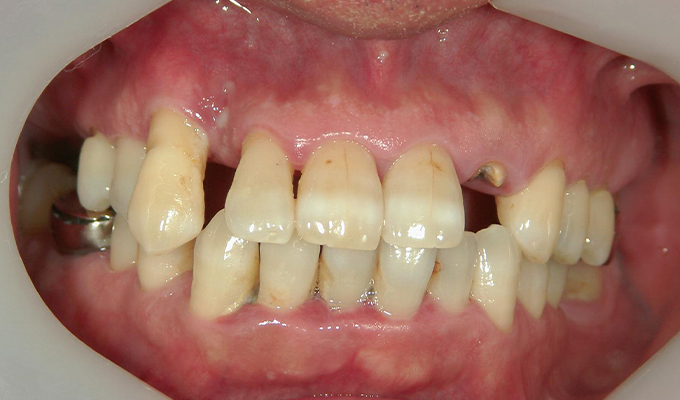

case1インプラントとメタルボンドブリッジの症例

初回メンテナンス時(2014年)

- 初診時の年齢

- 60代女性(2010年)

- 主訴

- ちゃんと咬めるようになりたい。最近孫が生まれたから一緒に歌ったりしたいけど、今は歌うこともできないから・・・・。と

- 治療内容

- 5年ほど前に入れ歯を作ったそうですが合わなかったので使用してなかったせいか前歯がグラグラになっていて今にも抜けそうな状態でした。

保存が難しい歯を抜歯し、上はインプラント8本、下は奥歯にインプラント4本埋入しました。

補綴は変色しないメタルボンドを選択されたので治療完了して11年経過してもとてもきれいな状態で維持されています。

初診時にお話しされていたお孫さんも中学2年生になったそうで、歯の治療をしたおかげで充実した毎日が送れてます、とメンテナンス時もいつも嬉しそうにされています。